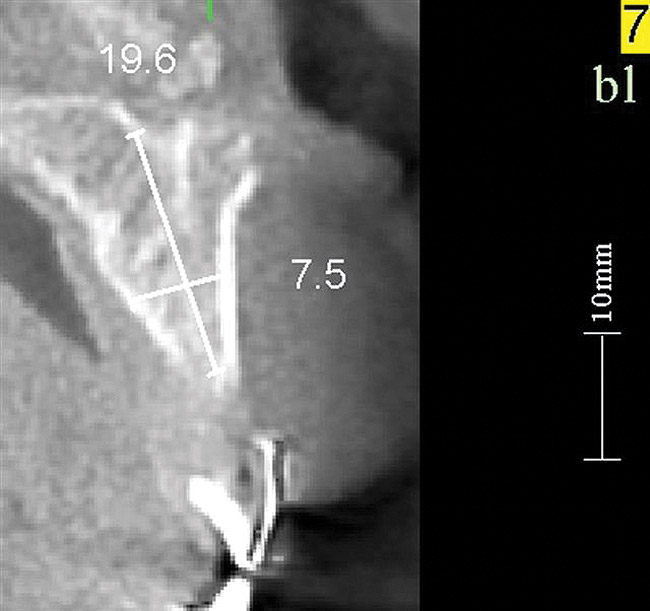

Figure 17   Volumetric characterization of the residual alveolar ridge using CBCT: Fig 17 The coronal section of the maxilla reveals the cortical structure of the alveolar ridge associated with the missing right central incisor at the mid-root level. The buccal plate is identifiable and is characterized by little resorption. Fig 18  The saggital section of the maxillary alveolar ridge is displayed in relationship to the planned contour of the eventual implant crown. Fig 19 Importing DICOM files into planning software permits evaluation of the implant, abutment, and crown relationships with existing bone. These images readily characterize both the possible 6-mm mesiodistal width and the possible displacement of the implant 3-mm apical and 2-mm palatal to the planned gingival zenith.

Figure 18    Volumetric characterization of the residual alveolar ridge using CBCT: Fig 17 The coronal section of the maxilla reveals the cortical structure of the alveolar ridge associated with the missing right central incisor at the mid-root level. The buccal plate is identifiable and is characterized by little resorption. Fig 18  The saggital section of the maxillary alveolar ridge is displayed in relationship to the planned contour of the eventual implant crown. Fig 19 Importing DICOM files into planning software permits evaluation of the implant, abutment, and crown relationships with existing bone. These images readily characterize both the possible 6-mm mesiodistal width and the possible displacement of the implant 3-mm apical and 2-mm palatal to the planned gingival zenith.

Figure 18